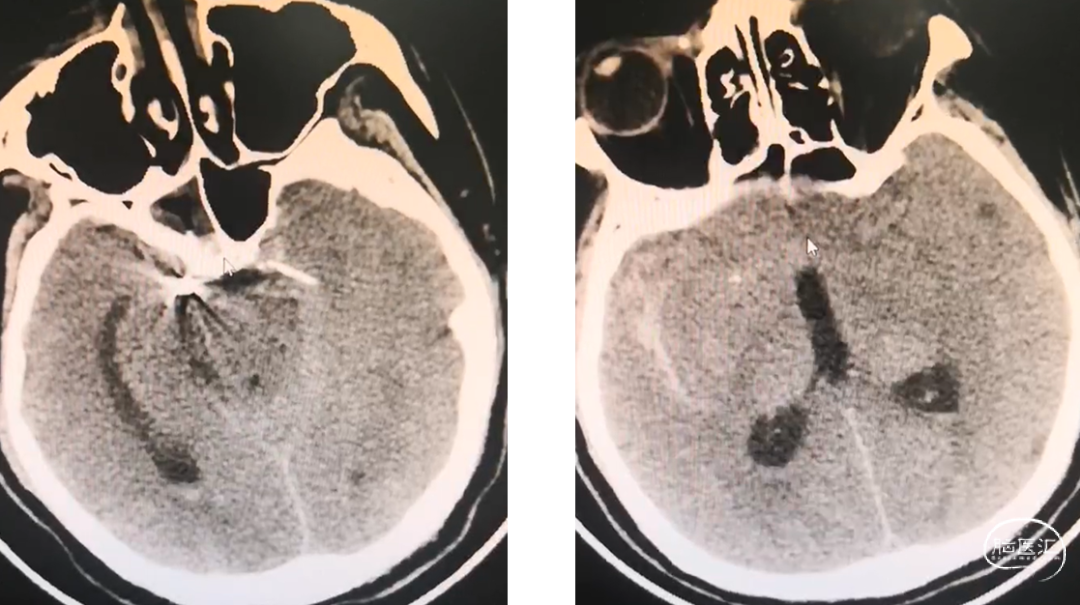

术后第一天CT

术后一周